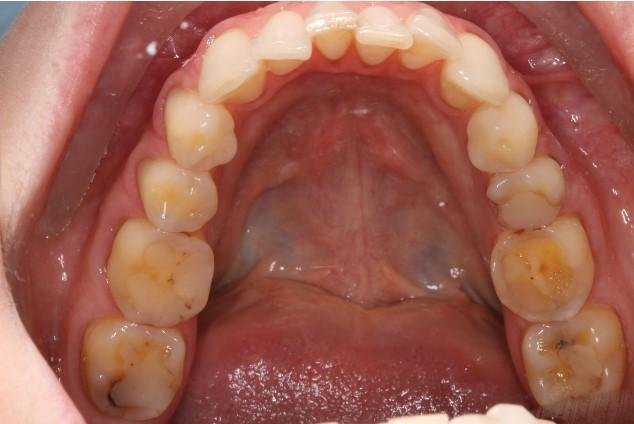

Как выглядел профиль пациента (фото)